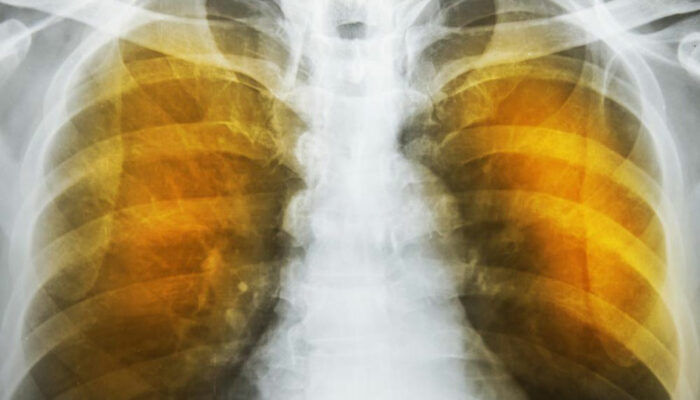

The next reaction is to cough out the irritants and the mucus. Severe forceful coughs can raise the pressure in the alveoli considerably and can rupture their exceedingly thin walls. The reduction of area for gas transfer and the loss of elastic tissues in the lungs reduces the capacity of the lungs to expel air. This reduces the intake volume of fresh air during breathing and can also lead to infections. These conditions produce the characteristic symptoms of wheezing, tightness in chest, labored breathing and coughing. These are also indications as well as symptoms of severe asthma.

The symptoms of emphysema are exceedingly severe and cause considerable damage to the lungs before the symptoms even show up. Generally, one feels a lack of energy and the tendency to skip some of the common daily routines. It progresses from slight difficulty in breathing to wheezing and then to a persistent cough that does not go away. One starts to feel a tightness in the chest and feels short of breath on exertion. Tiredness and persistent cough become constant.

As the deterioration continues, the alveoli lose their strength and start rupturing. In extreme cases, there may be large scale destruction which leads to empty spaces in lungs called bullae. This would reduce the functional area of the lung which in extreme cases call for surgical removal. In an extremely rare condition, large scale rupture of alveoli can cause a condition called pneumothorax and the collapse of the lung, a very serious condition, which can be fatal. The best thing one can do is stop exposure to irritants.